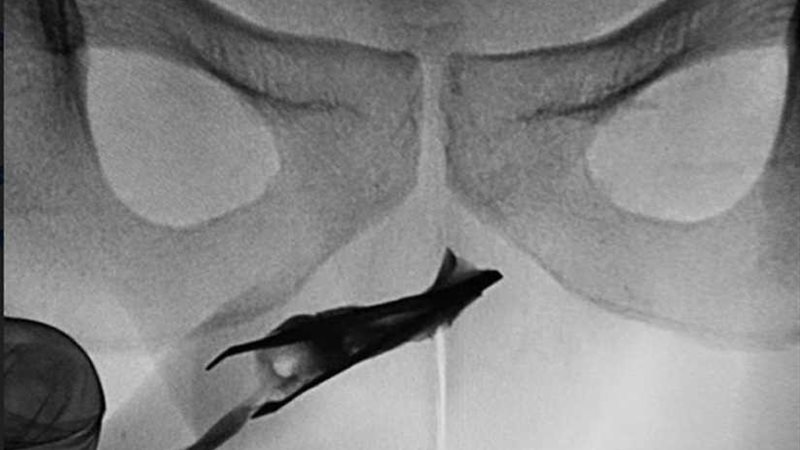

وحسبما ذكرت صحيفة "مترو" البريطانية، كشفت الأشعة السينية عن مكان وجود الملقاط ، الذي يظهر الطرف المغلق ، في مجرى البول بصلي في الأعلى.